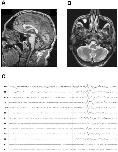

Figure 1. The patient presents with cerebellar atrophy and epilepsy. (A) Brain MRI section showing marked atrophy of the cerebellar vermis (T1-weighted image). (B) Brain MRI section showing slight atrophy of the cerebellar hemispheres (T2-weighted image). (C) Interictal EEG showing a frontotemporal spike, most prominent in the temporal leads (FT10, T8, TP10).